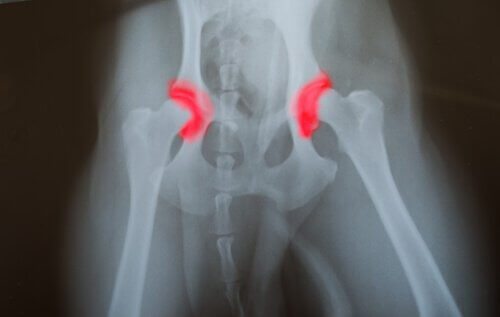

Jopa 25 % eläinlääkärikäynneistä liittyy ortopedisiin ongelmiin ja nivelrikkoon. Ainakin neljäsosassa näistä tapauksista ongelma johtuu epätasapainoisesta ruokavaliosta, joka sisältää vähän kalsiumia ja muita koiralle välttämättömiä ravintoaineita.

- Lonkkavika

Tutkimuksessa verrattiin isoja koiria, joiden ruokavalio oli tasapainossa, saman kokoisiin koiriin, joiden ruokavalio oli epätasapainoinen. Tasapainoista ruokavaliota noudattavilla koirilla esiintyi vähemmän liian nopeaan kasvuun yhdistettyjä sairauksia. Lonkkavika oli yksi yleisimmistä yliruokituilla isoilla koirilla esiintyvistä ongelmista.